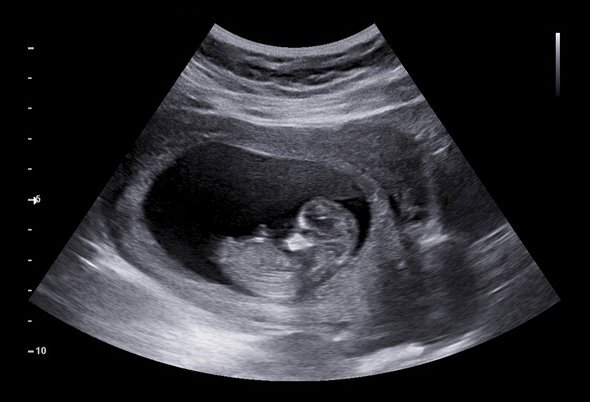

Селективные аборты стали популярны, как только врачи научились определять пол эмбриона в утробе с помощью ультразвука. Эта практика стала доступна медикам по всему миру в 80-е. Она была особенно популярна в Китае, где государство пыталось контролировать перенаселение с помощью политики «одна семья — один ребенок».

Фото: Shutterstock / Fishman64